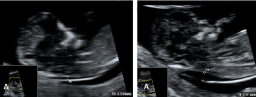

Ecografía de la translucencia nucal

La ecografía de la derecha muestra a un bebé con un cribado positivo que resultó tener un síndrome de Down. La translucencia nucal (o pliegue nucal) por ecografía se ve como un espacio negro en la parte posterior del cuello, acotado por las marcas del ecografista. El bebé de la izquierda...

Ecografía para medir al feto

En la ecografía 2D de este feto de 12 semanas, podemos apreciar la medida cráneo-caudal o CRC (desde la cabeza hasta la rabadilla o coxis), que en este caso es de 6,2 centímetros. Estirado, el bebé mide más -algo más de 10 centímetros-, pero los especialistas suelen tomar esta medida, más...